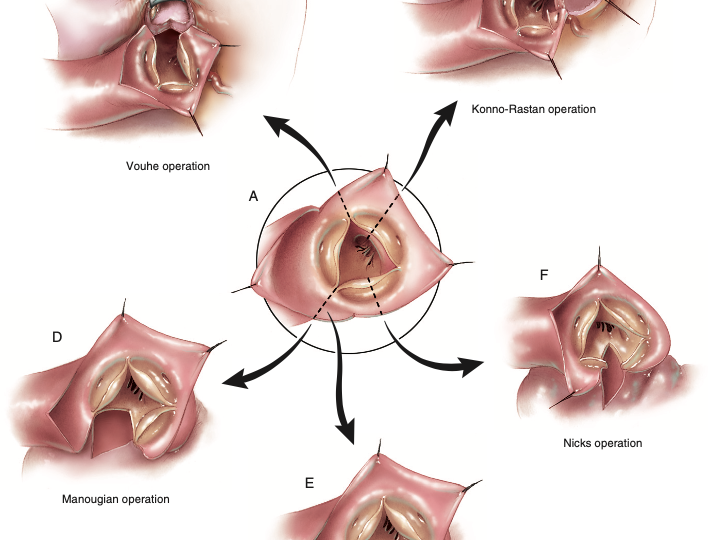

A raiz da aorta forma a via de saída do ventrículo esquerdo, iniciando ao nível das bases de cada…